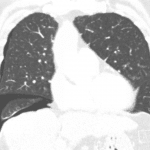

- Thin curvilinear density along the lateral aspect of the right hemithorax

- Loculated pneumothorax

Thin curvilinear density along the lateral aspect of the right hemithorax which may represent a pneumothorax versus external artifact. Recommend right-side-up decubitus radiographs or CT for further evaluation.